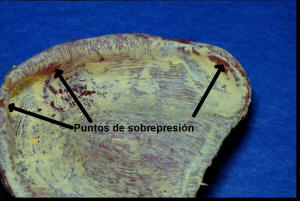

- Evaluar puntos de sobre presión , con pasta indicadora de

- En la imagen derecha inferior se observan las superficies de

sobrepresión, que deben ser aliviadas con fresa adecuada

| Zona de sobrepresión que muestra el color

rosa del acrílico |

Estos problemas pueden ser

solucionados durante la consulta dental, dado que solo requiere la

eliminación del problema con instrumental rotatorio y el posterior pulido

con pómez y cepillo. |